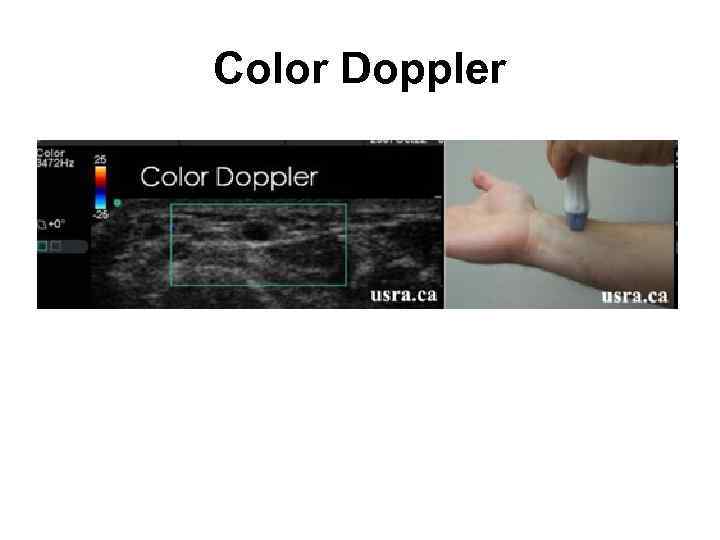

Цветовой допплер (Color Doppler)

Цветовой допплер (Color Doppler)

Color Doppler

Color Doppler

Цветовой допплер (Color Doppler) • выделение на эхограмме цветом (цветное картирование) характера кровотока в области интереса. • Кровоток к датчику принято картировать красным цветом, от датчика - синим цветом. • Турбулентный кровоток картируется сине-зеленожелтым цветом. • Цветовой допплер применяется для исследования кровотока в сосудах, в эхокардиографии.

Цветовой допплер (Color Doppler) • выделение на эхограмме цветом (цветное картирование) характера кровотока в области интереса. • Кровоток к датчику принято картировать красным цветом, от датчика - синим цветом. • Турбулентный кровоток картируется сине-зеленожелтым цветом. • Цветовой допплер применяется для исследования кровотока в сосудах, в эхокардиографии.

Цветовой допплер • Кровоток к датчику принято картировать красным цветом, • от датчика - синим цветом. • Турбулентный кровоток картируется сине-зелено-желтым цветом.

Цветовой допплер • Кровоток к датчику принято картировать красным цветом, • от датчика - синим цветом. • Турбулентный кровоток картируется сине-зелено-желтым цветом.